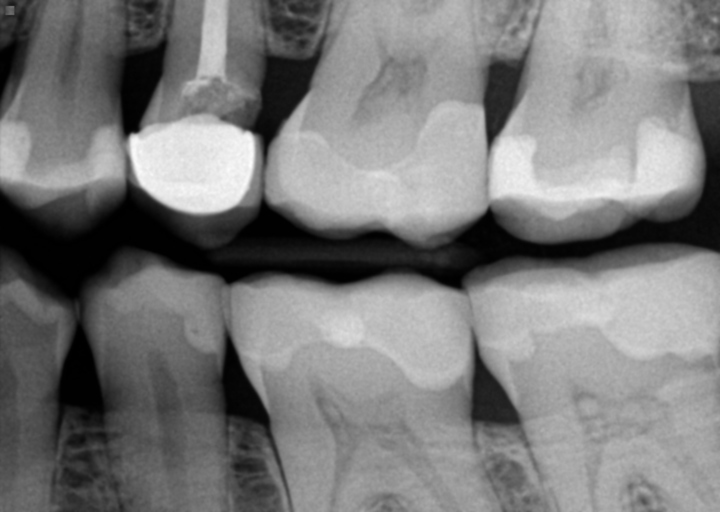

I have braces and a root canal done on my last bottom left molar. I also have an existing crown next to the root canal tooth. I have had two adjustments to my new crown and the dentist told me the pain is from my braces shifting my teeth. I can see that my crown is to high and there is a dark line by my gums. I have pain every time i eat or floss on that tooth. I feel like my dentist is wrong.

If your dentist hasn't taken an x-ray, you need to have them take one.  Crowns are placed on teeth that have large decay, cracks, restorations replaced that are too large to place a filling again, after a root canal, and for cosmetic reasons.  Most people do not crown molars for cosmetic purposes, therefore more than likely the tooth was not a solid tooth prior to the crown being placed.  The dark line you are seeing by the gums is many times from the underlying metal substructure of the crown or an amalgam tattoo.  Pain when eating and flossing on one specific tooth usually indicates an issue with the tooth.  If you are hitting that tooth first (hyper occlusion), you can create unnecessary trauma to the tooth, which can create pulpitis (inflammation of the pulp).  You also have the right to a second opinion if you feel your dentist is not listening to your concerns as a patient.